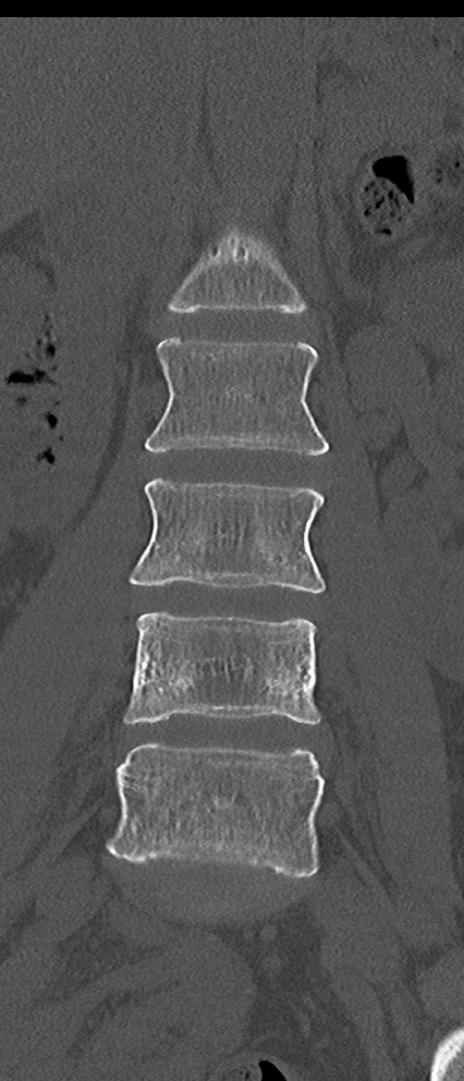

【整形】TIPS症例4 腰椎CT(冠状断像)

腰椎CT

矢状断像